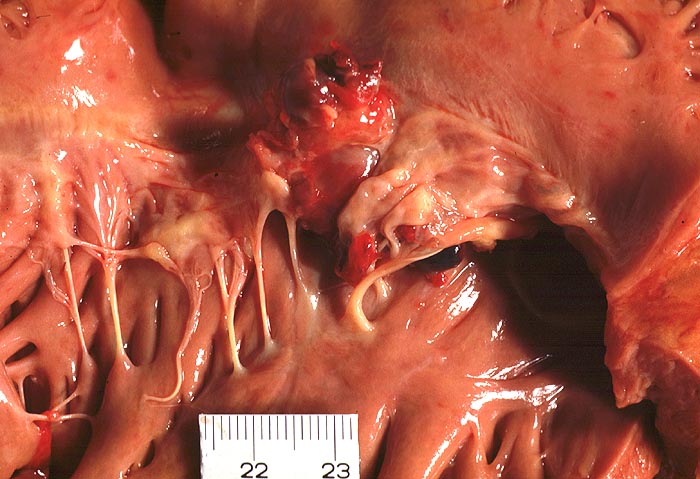

Ulzeropolypöse Endokarditis

Trikuspidalklappe

Partiell destruierte Klappensegel mit polypoiden Vegetationen.

Nachweis von Staphylokokken in der Blutkultur.